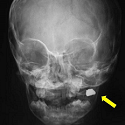

Metallic foreign body in the cheek mimicking a chronic facial abscess.

Ali Akhaddar, Mohammed Akhiri

PAMJ. 2013; 16: 136. Published 11 December 2013